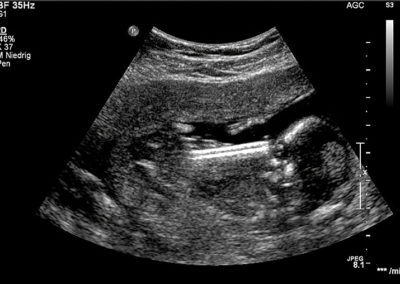

The Intra-Uterine-Shunt (IUS) is used to treat fetuses with obstructive urinary tract disorders. The shunt consists of a 25 mm long, fine Nitinol wire mesh, which is sealed from the inside with a silicone membrane. The IUS is inserted percutaneously between the fetal bladder and the amniotic cavity under sonographic monitoring.

The patented Intra-Uterine-Shunt unfolds upon deployment, creating a 2.6 mm opening to drain the fluid. The flexible material allows a smaller cannula diameter of 18 Gauge compared to the conventional 15 Gauge. This reduces the risks of puncture trauma and serious complications (such as PROM). In addition, the flexible design adapts to the movements of the fetus.

• Cannula tip and shunt are highly visible in ultrasound